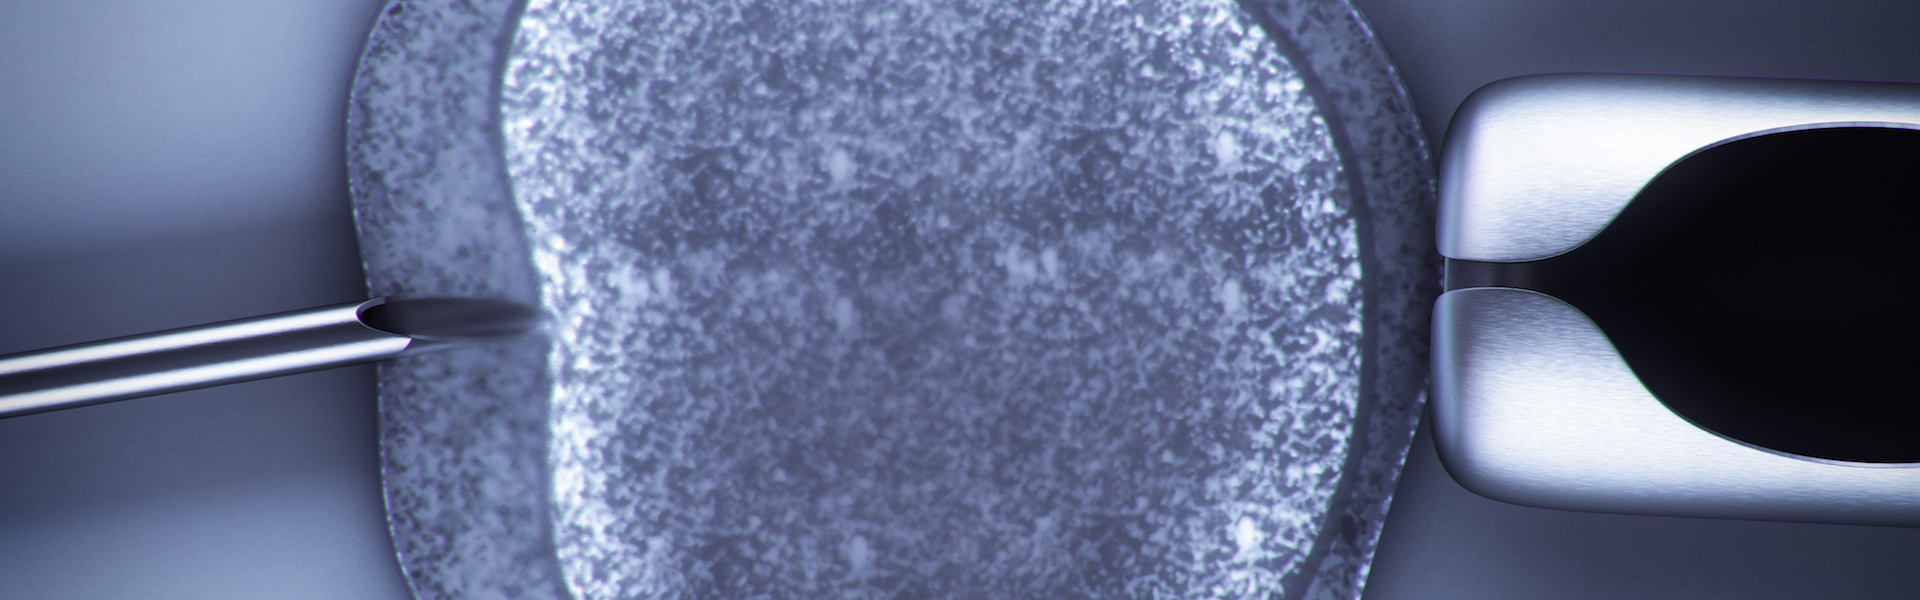

Preimplantációs genetikai vizsgálat (PGD) elvégzésére a mesterséges megtermékenyítés (in vitro fertilizáció, IVF) és az embriótranszfer (ET) során nyílik lehetőség. A vizsgálat elvégzéséhez általában harmadik napon, az 5-10 sejtes preembrióból mikromanipulátor segítségével kivesznek egy vagy két sejtet (blasztomert). Ehhez a preembriót először kalcium- és magnéziummentes tápoldatba helyezik a sejtek közötti szoros kapcsolatok oldására. A mikromanipulátor tartópipettájával rögzített preembrió zona pellucidáját lézerrel, savas oldattal vagy mechanikusan megnyitják, majd biopsziás pipetta segítségével óvatosan kiemelik a blasztomert.

A petesejt első, illetve második sarki testéből (a petesejthez kapcsolódó két képlet, amely szintén tartalmazza a petesejt genetikai állományát, de nem vesz részt a megtermékenyülés utáni folyamatokban) is elvégezhető a vizsgálat. Ebben az esetben azonban értelemszerűen csak a petesejtről kapunk információt. Lehetőség nyílik továbbá a megtermékenyítést követő ötödik napon, hólyagcsíra (blasztociszta) stádiumban, az úgynevezett trophektoderm sejtek biopsziájára. Az utóbbi években az ún. vitrifikációs technikák fejlődése révén – melynek alkalmazásával a mélyhűtött blasztociszták felmelegítés utáni életképessége lényegesen jobb, mint a korábban alkalmazott mélyfagyasztási módszerekkel – az ötödik napi mintavétel kezd egyre jobban elterjedni.